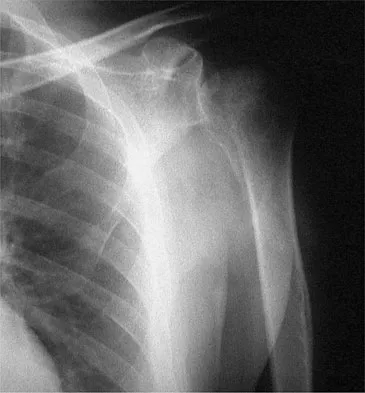

Figures 52a and 52b show the plain radiographs of a 12-year-old girl who has right distal leg pain. She reports that symptoms are present with weight-bearing activities and improve with rest. Examination reveals diffuse tenderness over the distal tibial metaphysis and mild swelling. A photomicrograph of the biopsy specimen is shown in Figure 52c. What is the most likely diagnosis?

Explanation